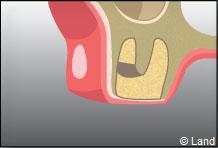

Une fois la dent enlevée, la cavité est nettoyée. En cas d’une dent souffrant d’inflammation, le tissu infecté sera également enlevé.

La fermeture de la cavité s’effectue souvent à l’aide de points de suture servant à réunir les bords de la gencive.